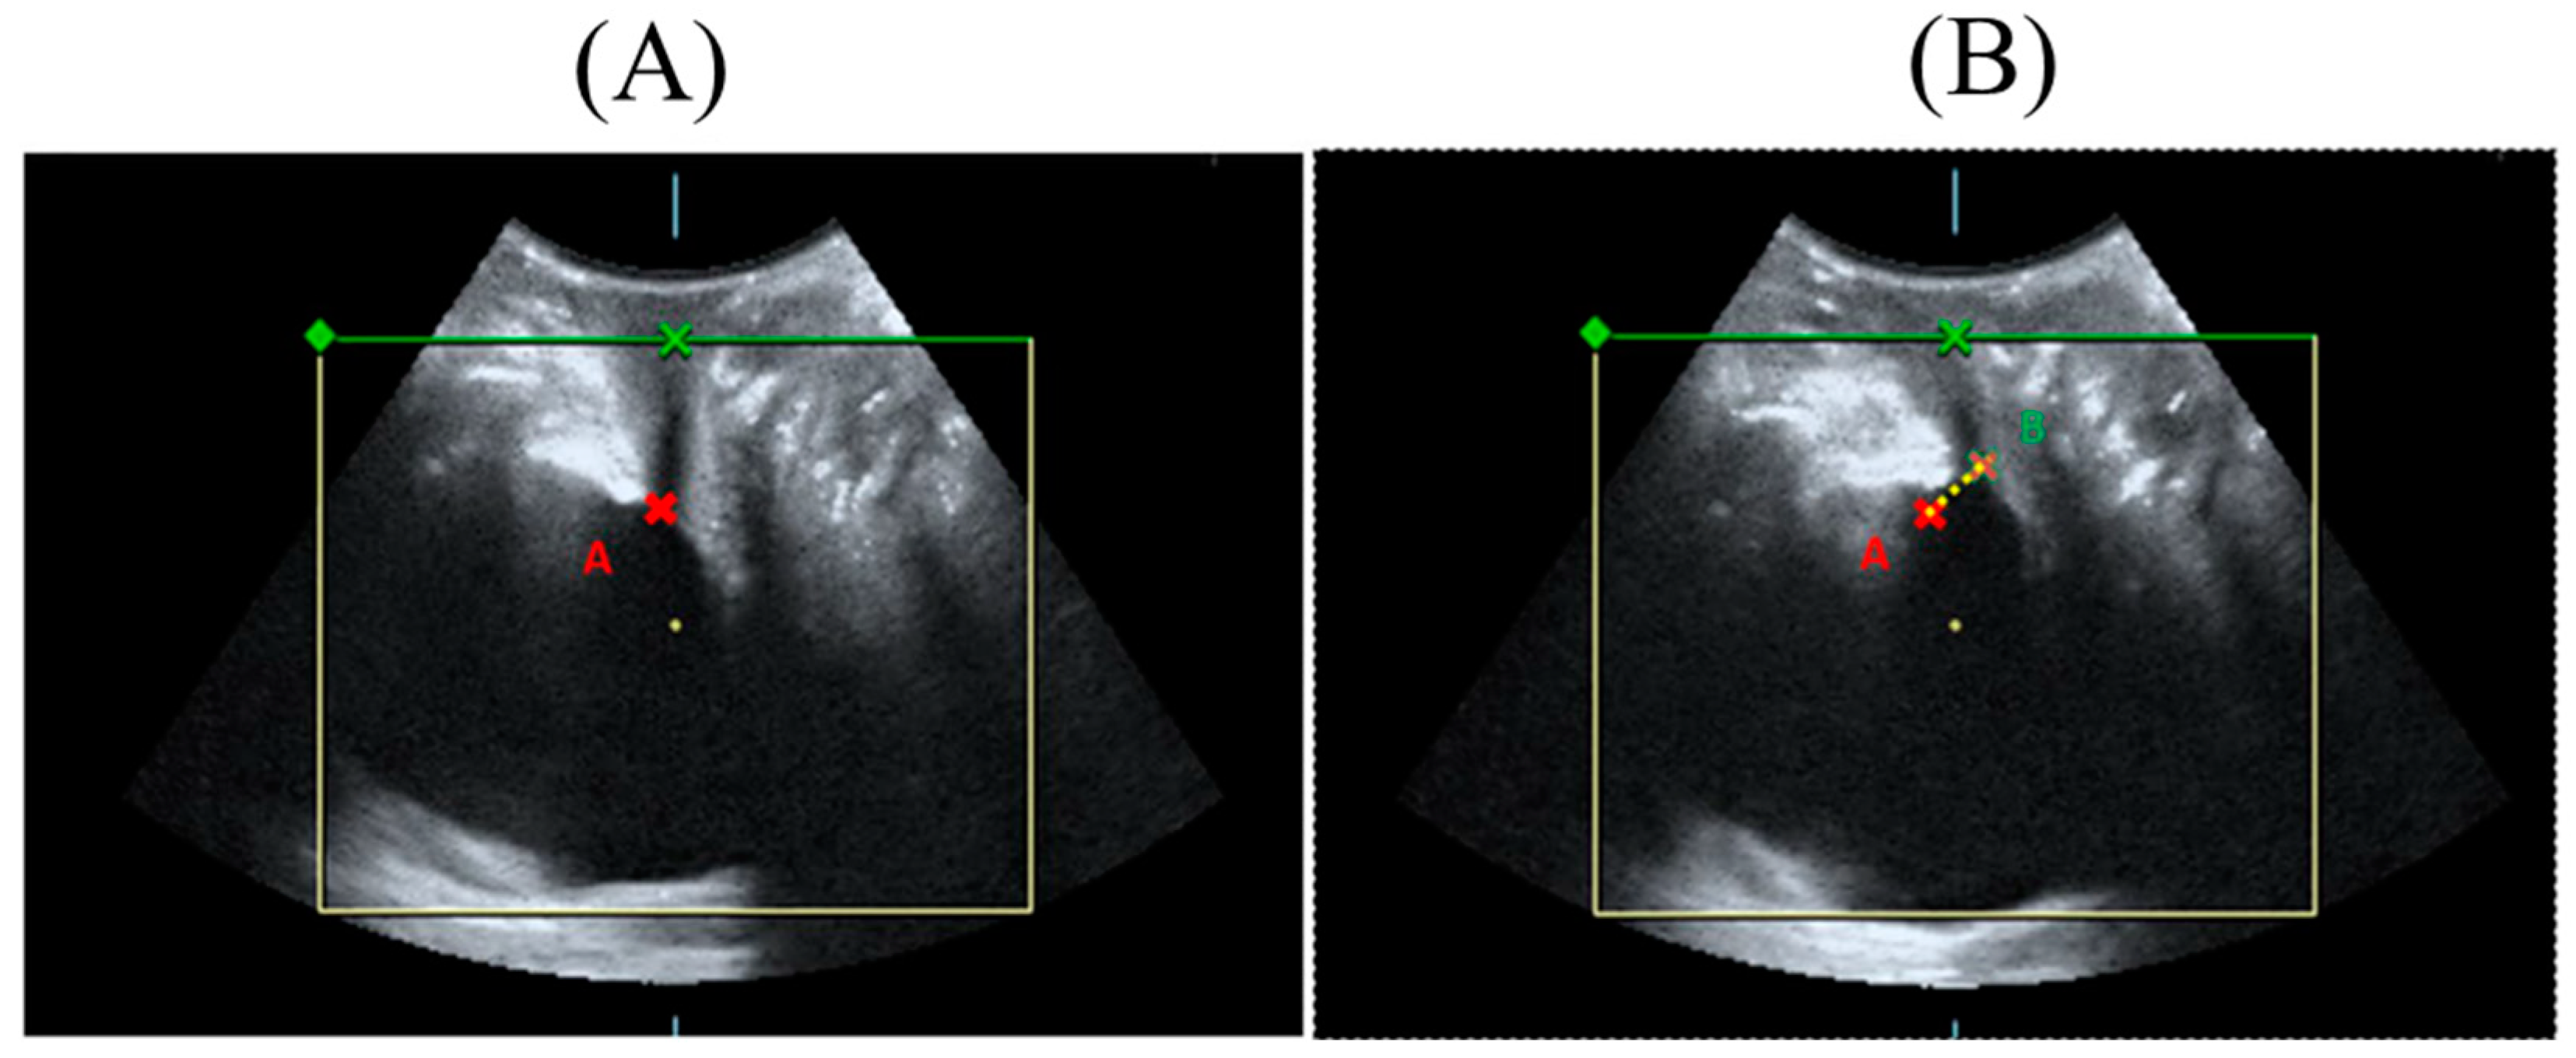

3.4. Effect of HIFEM Treatment on Bladder Neck Mobility in Ultrasound Topography

| n = 14 | Pre-Tx | Post-Tx 6M | p Value | |

|---|---|---|---|---|

| Bladder neck mobility (mm) | 1.2 ± 0.4 | 1.1 ± 0.3 | 0.34 | |

| Urethral area (mm²) | proximal | 0.8 ± 0.4 | 0.7 ± 0.2 | 0.58 |

| Resting | middle | 0.8 ± 0.3 | 0.8 ± 0.2 | 0.17 |

| distal | 2.3 ± 1.0 | 2.5 ± 1.2 | 0.44 | |

| Urethral area (mm²) | proximal | 4.1 ± 1.3 | 5.3 ± 17.2 | 0.34 |

| straining | middle | 0.8 ± 0.2 | 0.8 ± 0.3 | 0.17 |

| distal | 0.7 ± 0.2 | 0.6 ± 0.2 | 0.19 | |

| n = 14 | Rest | Stress | |||||

|---|---|---|---|---|---|---|---|

| Pre-Tx | Post-Tx 6M | p Value | Pre-Tx | Post-Tx 6M | p Value | ||

| Vaginal width | Proximal | 4.6 ± 0.5 | 4.4 ± 0.5 | 0.75 | 4.6 ± 0.5 | 4.4 ± 0.6 | 0.67 |

| Middle | 4.2 ± 0.4 | 4.2 ± 0.5 | 0.44 | 4.4 ± 0.5 | 4.2 ± 0.5 | 0.19 | |

| Distal | 4.3 ± 0.3 | 4.0 ± 0.4 | 0.05 * | 4.4 ± 0.5 | 4.1 ± 0.4 | 0.04 * | |

| Vaginal area | Proximal | 6.1 ± 1.6 | 4.0 ± 1.2 | <0.001 * | 6.9 ± 1.3 | 5.2 ± 2.0 | 0.002 * |

| Middle | 5.6 ± 1.2 | 4.0 ± 1.1 | 0.002 * | 6.5 ± 1.0 | 4.8 ± 1.6 | 0.003 * | |

| Distal | 5.7 ± 1.4 | 4.1 ± 1.1 | 0.001 * | 6.4 ± 1.2 | 4.4 ± 1.3 | <0.001 * | |

| Levator hiatus | Area | 12.0 ± 2.7 | 10.2 ± 2.7 | 0.028 * | 13.5 ± 2.8 | 11.8 ± 3.4 | 0.024 * |

| Short axis | 4.5 ± 0.5 | 4.2 ± 0.5 | 0.104 | 4.7 ± 0.5 | 4.3 ± 0.5 | 0.013 * | |

| Long axis | 3.5 ± 0.6 | 3.4 ± 0.6 | 1.0 | 3.9 ± 0.6 | 3.7 ± 0.6 | 0.5 | |